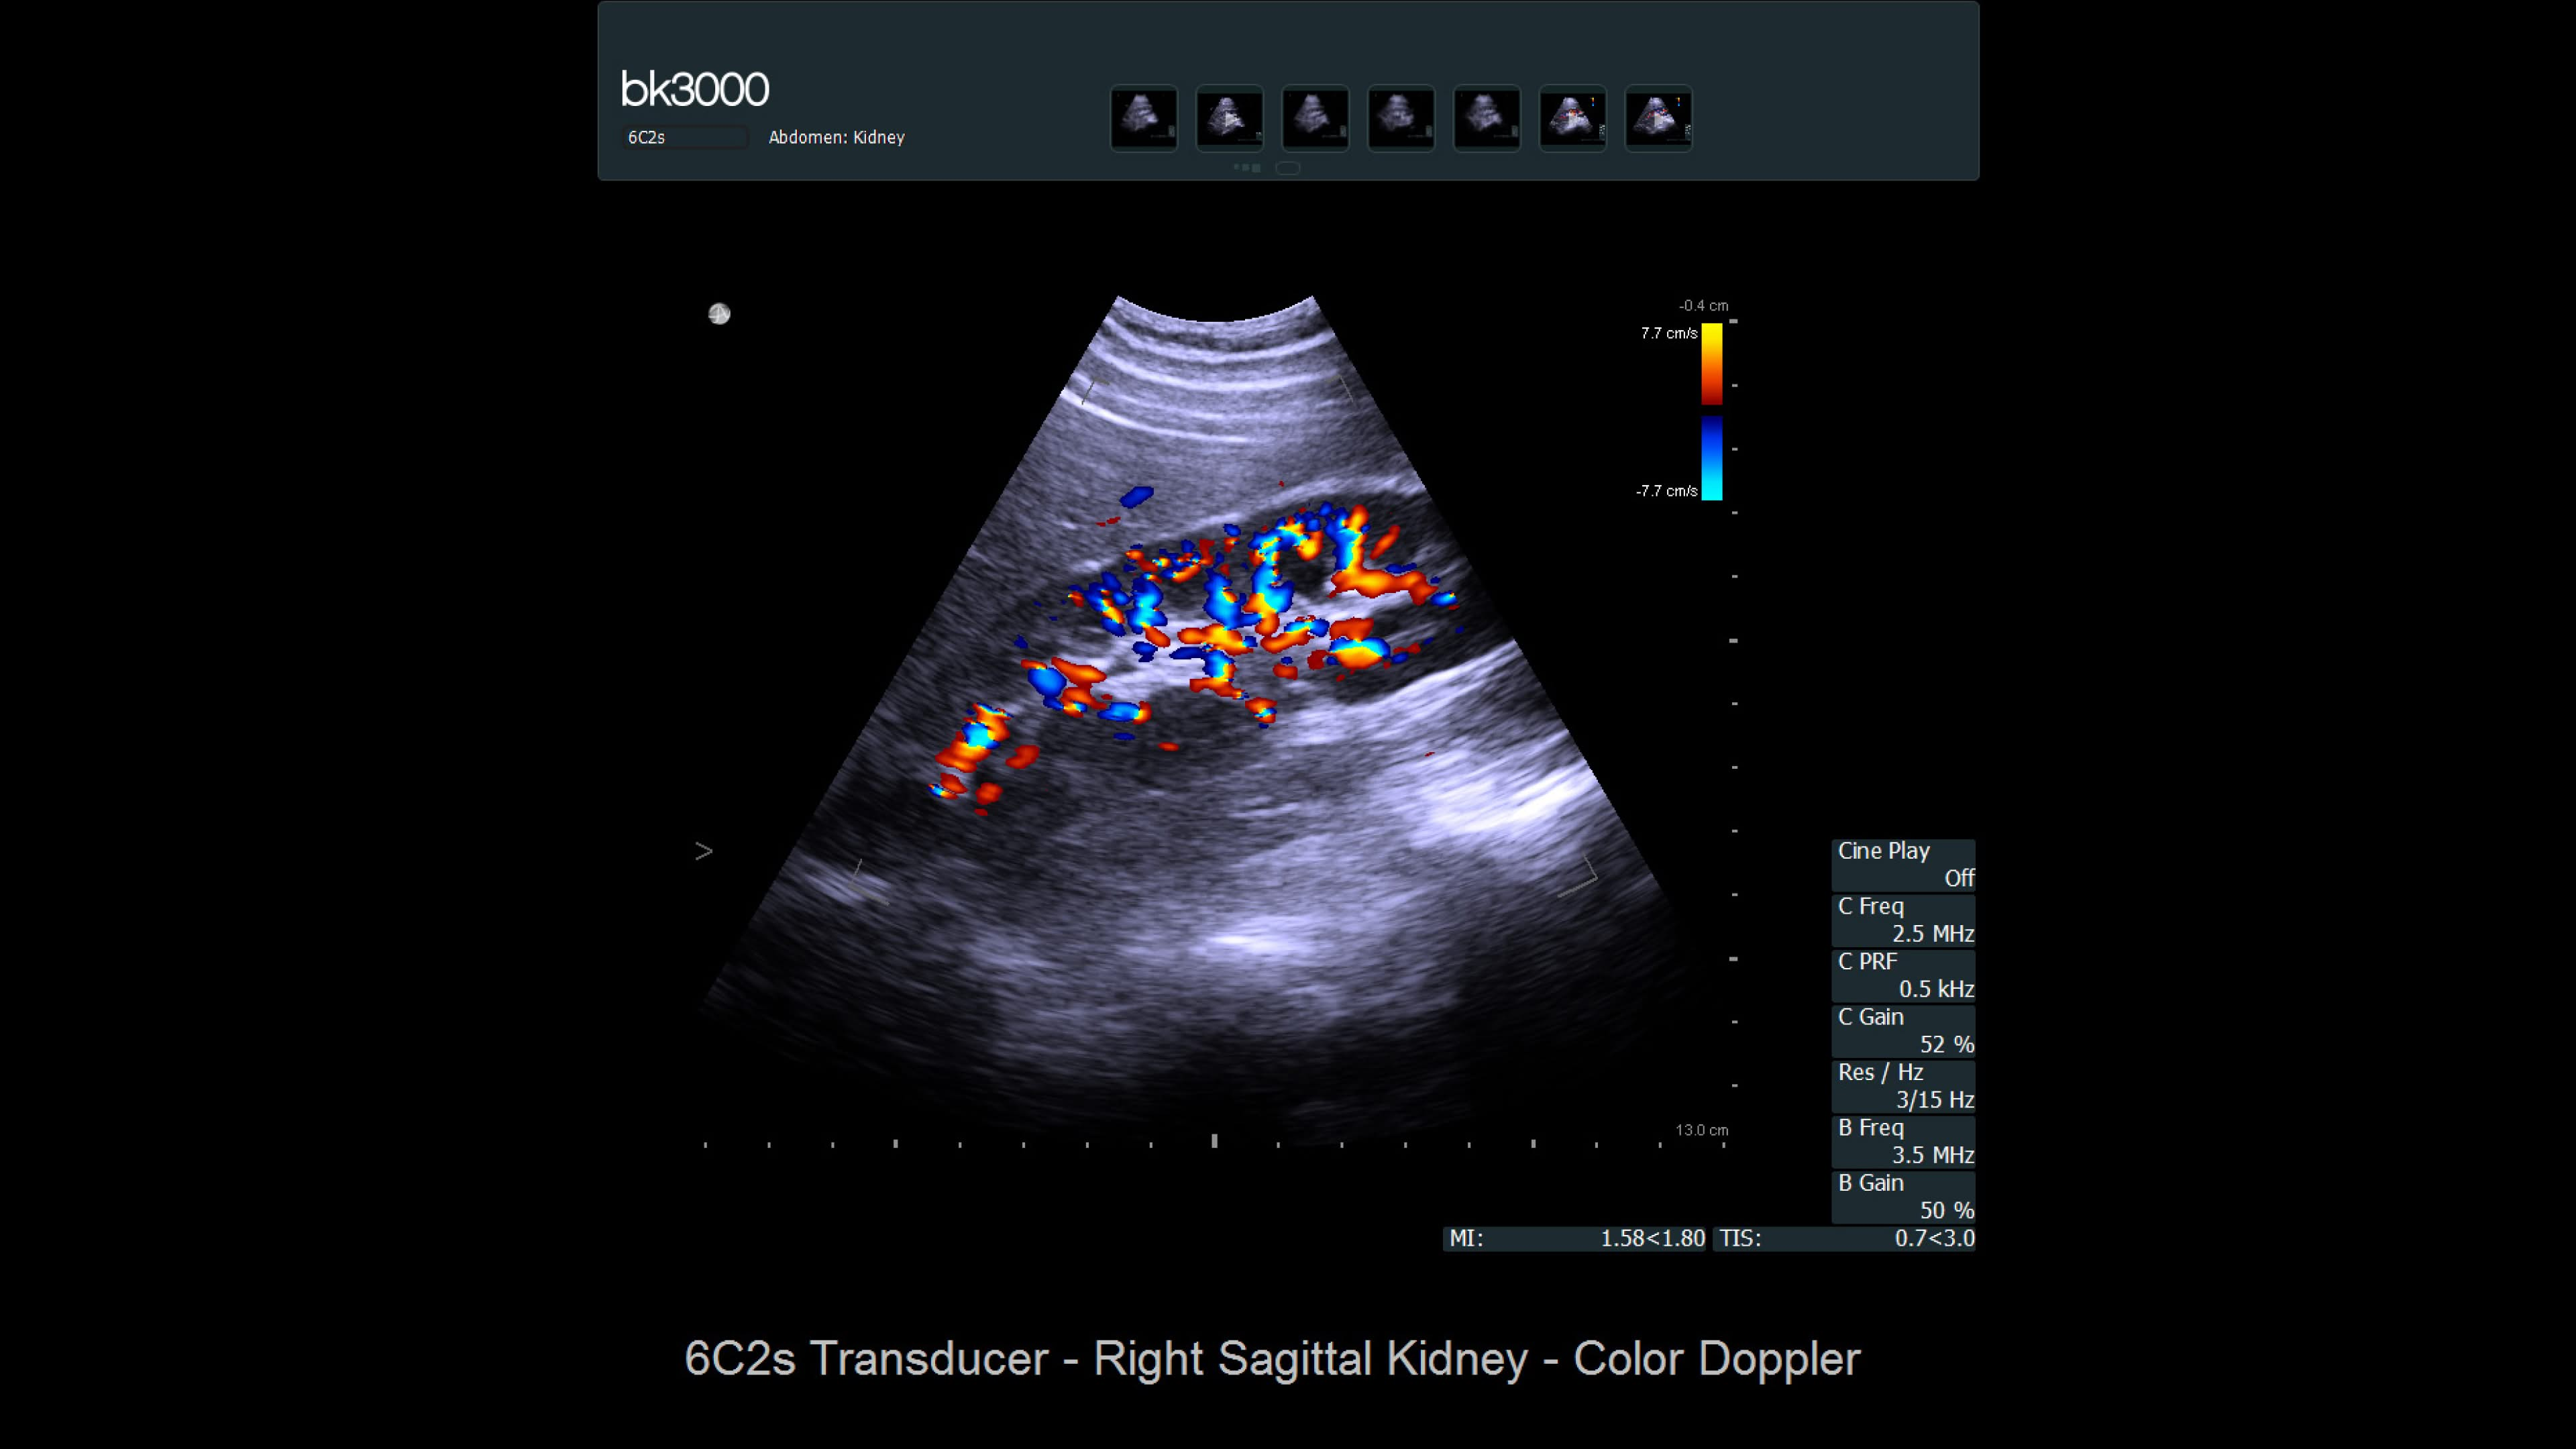

Ultrasound provides detailed information for kidney imaging, measurement, and biopsies. The bk3000 and bkSpecto systems help visualize fine anatomical details, see vascularization, measure blood flow, and locate kidney stones. The bkActiv, our flagship system, offers next-level imaging for prostate, renal, kidney, and bladder imaging, with sensitive Doppler for blood flow. Combined with sterilizable transducers, the bkActiv sets a new standard for surgical urology.